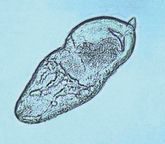

Prosthogonimus macrorchis(oviduct fluke)(一般に卵管吸虫と呼ばれる)体長5~7mm、洋ナシ型虫卵は、26~32 x 10~15㎛北アメリカの鳥類に寄生します。